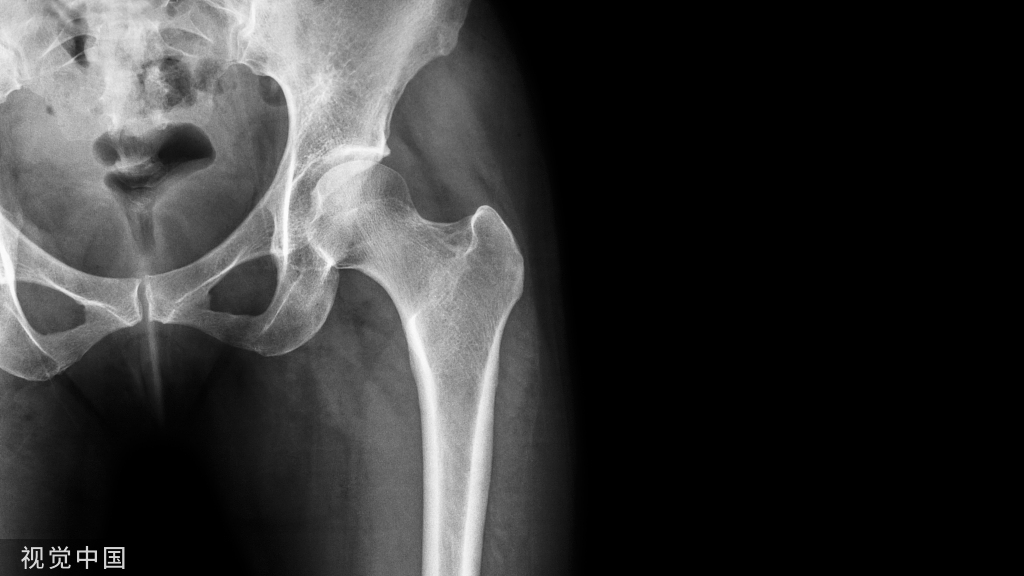

(八)髋关节

左侧股骨大粗隆处见不规则透亮线影,骨折处无明显分离、移位。左侧股骨大粗隆骨折。